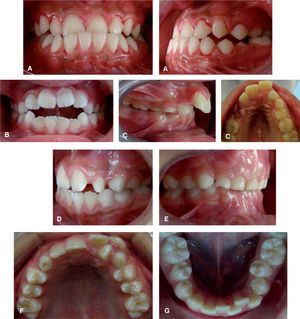

When analyzing the percentage distribution by gender, it was noted that, for females as well as for males, lingual interposition was the most prevalent since more than half of the children presented it; lip suction and onychophagia occupied second and third place respectively (Table II). The most prevalent malocclusion were open bite with a 35.1%, in second place, lower anterior crowding with a 26.4%; thirdly, upper anterior crowding with 19.6%, followed by anterior cross bite with 12.8%; overbite, 11.5%, edge to edge bite 9.5% and, finally, overjet with 7.4% (Figure 4).

In regard to the presence of malocclusions in relation to gender, the largest proportion was open bite with a 38.15% for females, and 32.39% for males; lower anterior crowding with 28.94% in females and 23.94% in male. In primary dentition, the highest prevalence was the mesial terminal plane with 21.05% in females and 15.49% in males. In the permanent dentition class I molar was more prevalent with 36.84% in females and 43.66% for males.

Posterior crossbite was observed in the 14.47% girls, while in males, it was 11.26%.

It was observed that the mesial step was the most prevalent in the first dentition cases and for the second dentition it was the Angle’s class I, by which the studied patients had a tendency to the normo-occlusion in a high percentage (Figures 5and6).